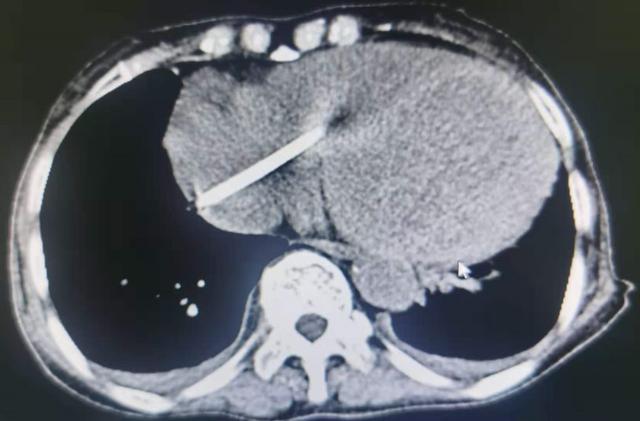

家人发现后 , 立即将老人送到当地医院 。 拍片发现 , 断在体内的导管就像断了线的风筝 , 随着血流从颈静脉“游”到上腔静脉 , 有一部分到达心脏 , 并“横躺”在心脏里 , 还随着心脏搏动而跳动 。

当晚 , 老人被紧急转入湖南省人民医院介入血管外二科 。 欧阳尚副主任医师查看CT结果发现 , 果然 , 断了的管子一端顶着腔静脉;一端顶着心脏 , 圈套器取异物很有挑战 。 为了尽早解除隐患 , 医生安排老人次日接受微创手术 。